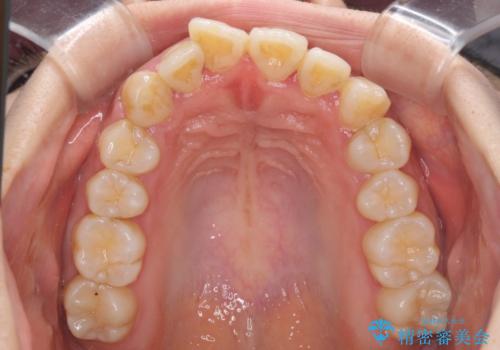

軽微な歯列不正をワイヤー矯正で整える

- 上顎歯列と下顎前歯の叢生を気にして来院された患者様です。

上顎からワイヤー矯正を開始し、終了間際から下顎前歯の叢生解消するよう計画しました。

部分矯正でしたが、咬み合わせに違和感が出ることなく気になる部分を改善させることができました。